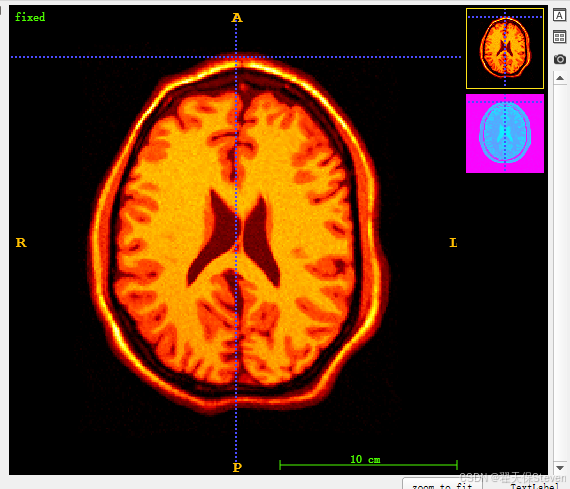

6)如上图所示,右上角箭头点一下,有一个Overlays,点击里面是moving,再后面一层有一个 opacity滑动条,往左滑到头就是fixed,往右滑到头就是moving,通过滑动可以实现直观观察。如下图所示,就是两张图分别权重为0.5的样子。

7)如果两张图像都是灰度图不太明显,可以将两张图的Color Map改一下,也是箭头点一下,点Color Map,fixed选择Hot,moving选择Cool。如下所示。

8)再次融合,就能看出差异了。